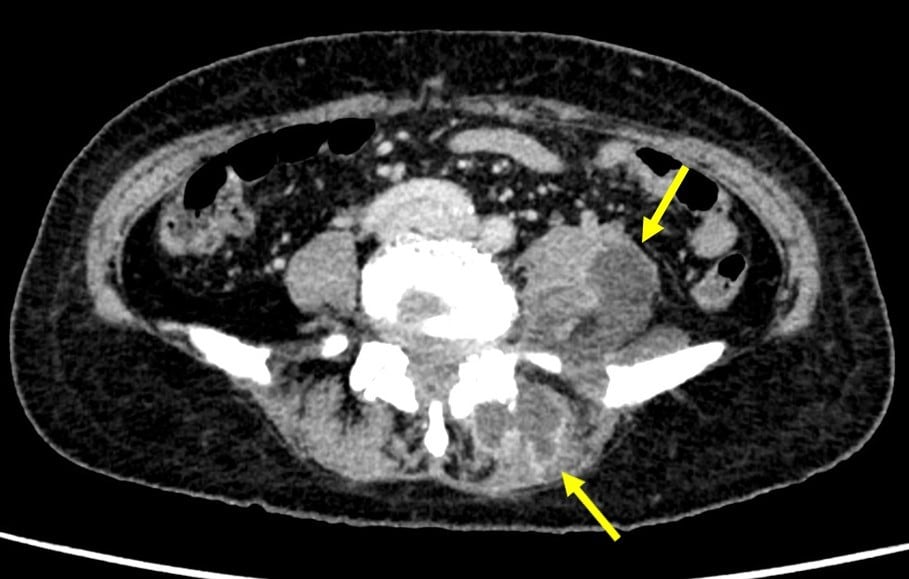

乳癌術後の再発・転移の検索目的で行われた単純CTで左腸腰筋膿瘍が疑われた。当科にCTガイド下ドレナージによる治療が依頼された。造影CTにて膿瘍は左大腰筋から左脊柱起立筋や左腰方形筋にかけて広範囲に認められた。形状は不整形で分葉状であり、辺縁に造影効果が認められ、内部は液体濃度の低吸収であり、隔壁も認められた。CTガイド下にドレナージカテーテルが膿瘍内に留置された。乳白色の膿汁がドレナージでき、ドレナージ後のCTでは膿瘍の縮小を認めた。

腸腰筋膿瘍の症状として、発熱、腰痛、psoas positionの三主徴が知られているが、実際に全てが揃う頻度は高くない。単純CTでは診断が困難な場合もあり、熱源不明で発見が遅れることもある。造影CTでは膿瘍が検出しやすくなり、さらにドレナージを行う上でも膿瘍腔の形状や範囲が確認できるため、非常に有用である。

熱源精査など全身検索の場合、造影は平衡相のみの撮影となっている。あらかじめ単純撮影は行われていたので、膿瘍鑑別のために、適量造影剤を注入後120秒後に撮影を行っている。

全身状態も良くないため、血管確保ルートも細目であったため、圧入は行っておりません。膿瘍のドレナージ前などは目的部位の動脈相もあれば穿刺前情報として有効と考えられる。